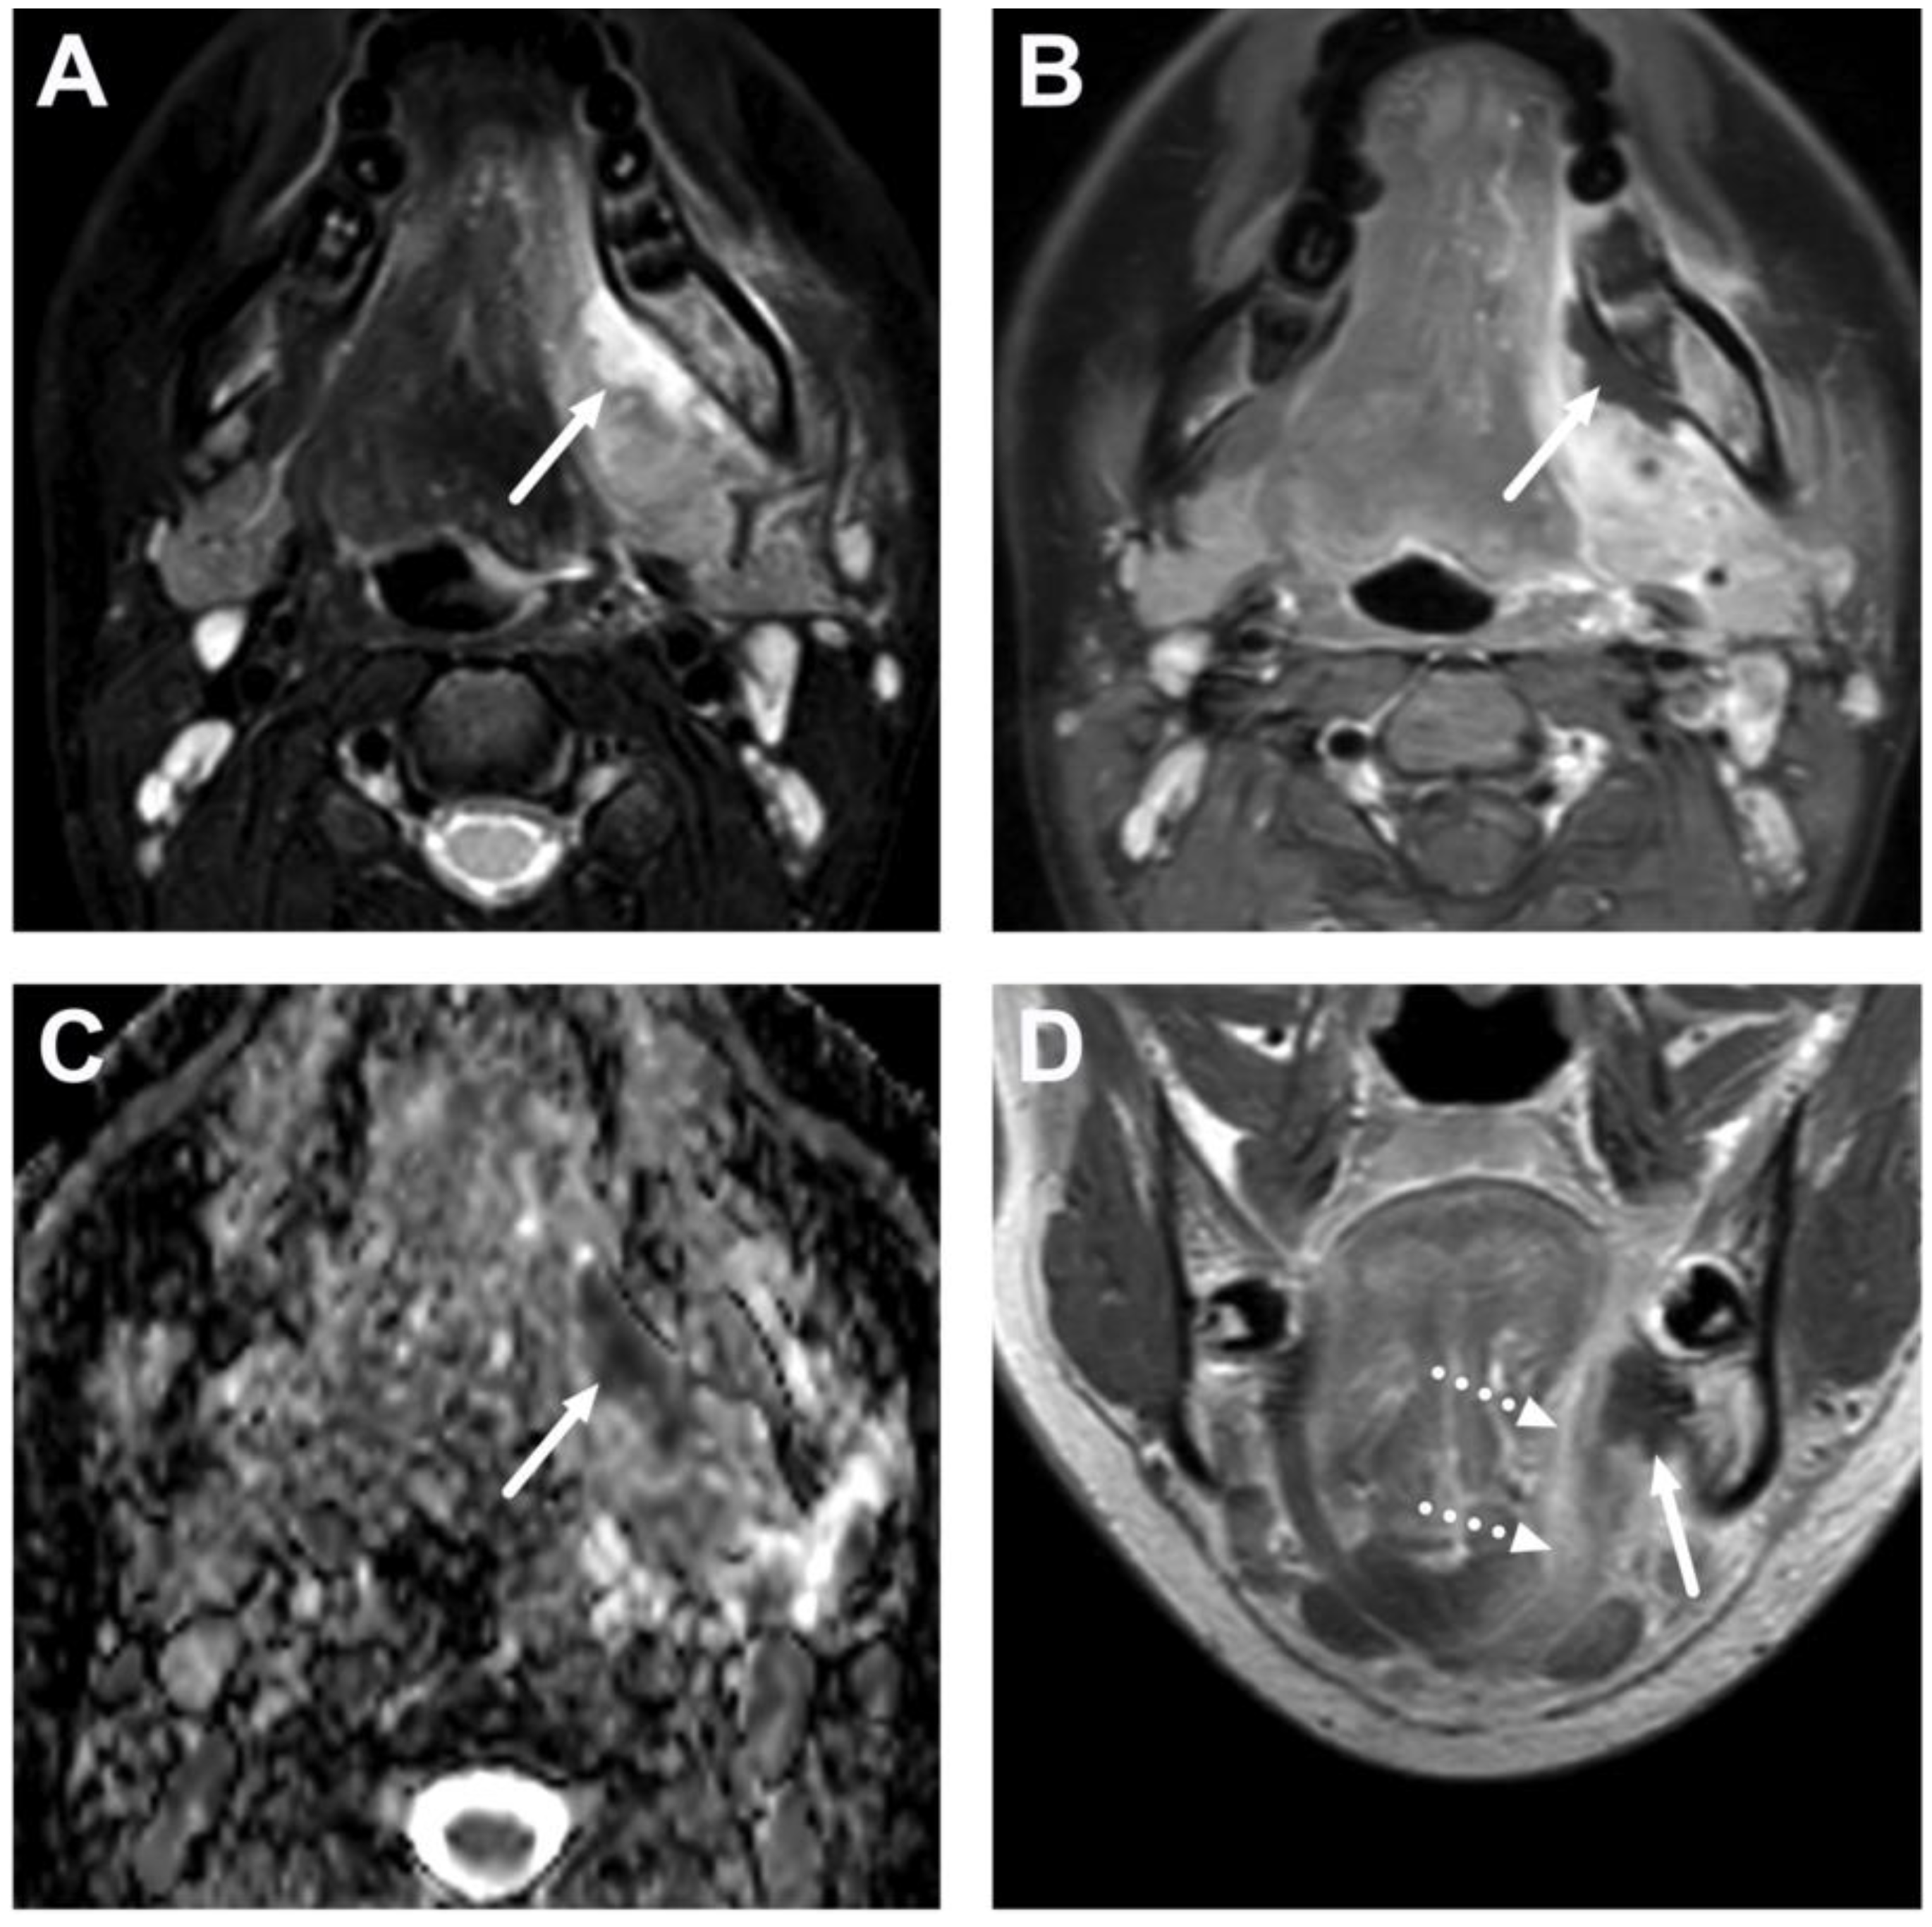

4.2. Retropharyngeal Abscesses and Suppurative Lymphadenitis

4.3. Oral Cavity

5.1. Lymphadenitis with Purulence vs. Necrosis

| Abscess | T1 SE T2 Dixon (water) DWI post-contrast T1 Dixon (water) | Non-enhancing collection with low ADC values enclosed in abnormally enhancing soft tissue edema. | Detection of an abscess usually requires operative consideration and exact abscess location, and extensions are useful in operative planning. | Abscesses may have an intermediate T2 signal content; blood products and/or postoperative status may complicate abscess assessment; necrotic lymph nodes may be misinterpreted as suppurative lymphadenitis. |